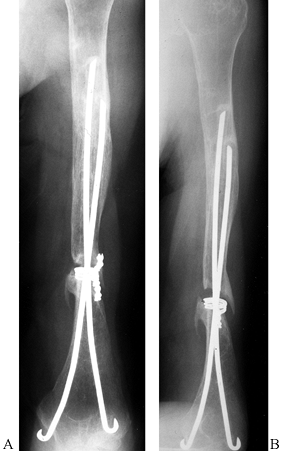

![]() |

|

Figure 15.29.

Anteroposterior radiograph illustrating the use of two Ender’s rods and #5 nonabsorbable suture tension band to stabilize an unstable, comminuted, two-part proximal humerus fracture in an elderly patient with osteopenic bone. |